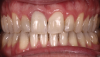

Fig 18. Bite interdigitation to finalize surgical orthodontic correction. After orthodontics, periodontal plastic surgery, bleaching, microabrasion, and restorative dentistry were performed.

Figure 18

Fig 19. Bite interdigitation to finalize surgical orthodontic correction. After orthodontics, periodontal plastic surgery, bleaching, microabrasion, and restorative dentistry were performed.

Figure 19

Fig 20. Bite interdigitation to finalize surgical orthodontic correction. After orthodontics, periodontal plastic surgery, bleaching, microabrasion, and restorative dentistry were performed.

Figure 20

As previously mentioned, adult patients requiring orthognathic surgery often have esthetic dentistry and/or prosthodontic requirements. These are usually addressed after the surgical orthodontic correction has been completed and many times complemented through periodontal plastic surgery to improve the gingival architecture. A case report depicting this type of situation is presented in Figure 8 through Figure 20. In many instances the orthodontist is required to lead the interdisciplinary team and make appropriate coordinations with other dental specialties.1,11